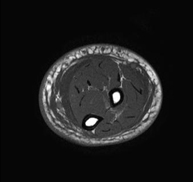

- Leg MRI

Examination to study injuries to tendons, muscles and peripheral nerves. Very useful for diagnosing fibrillar tears in twins. It lasts approximately 18 minutes. It is a radiation-free procedure.